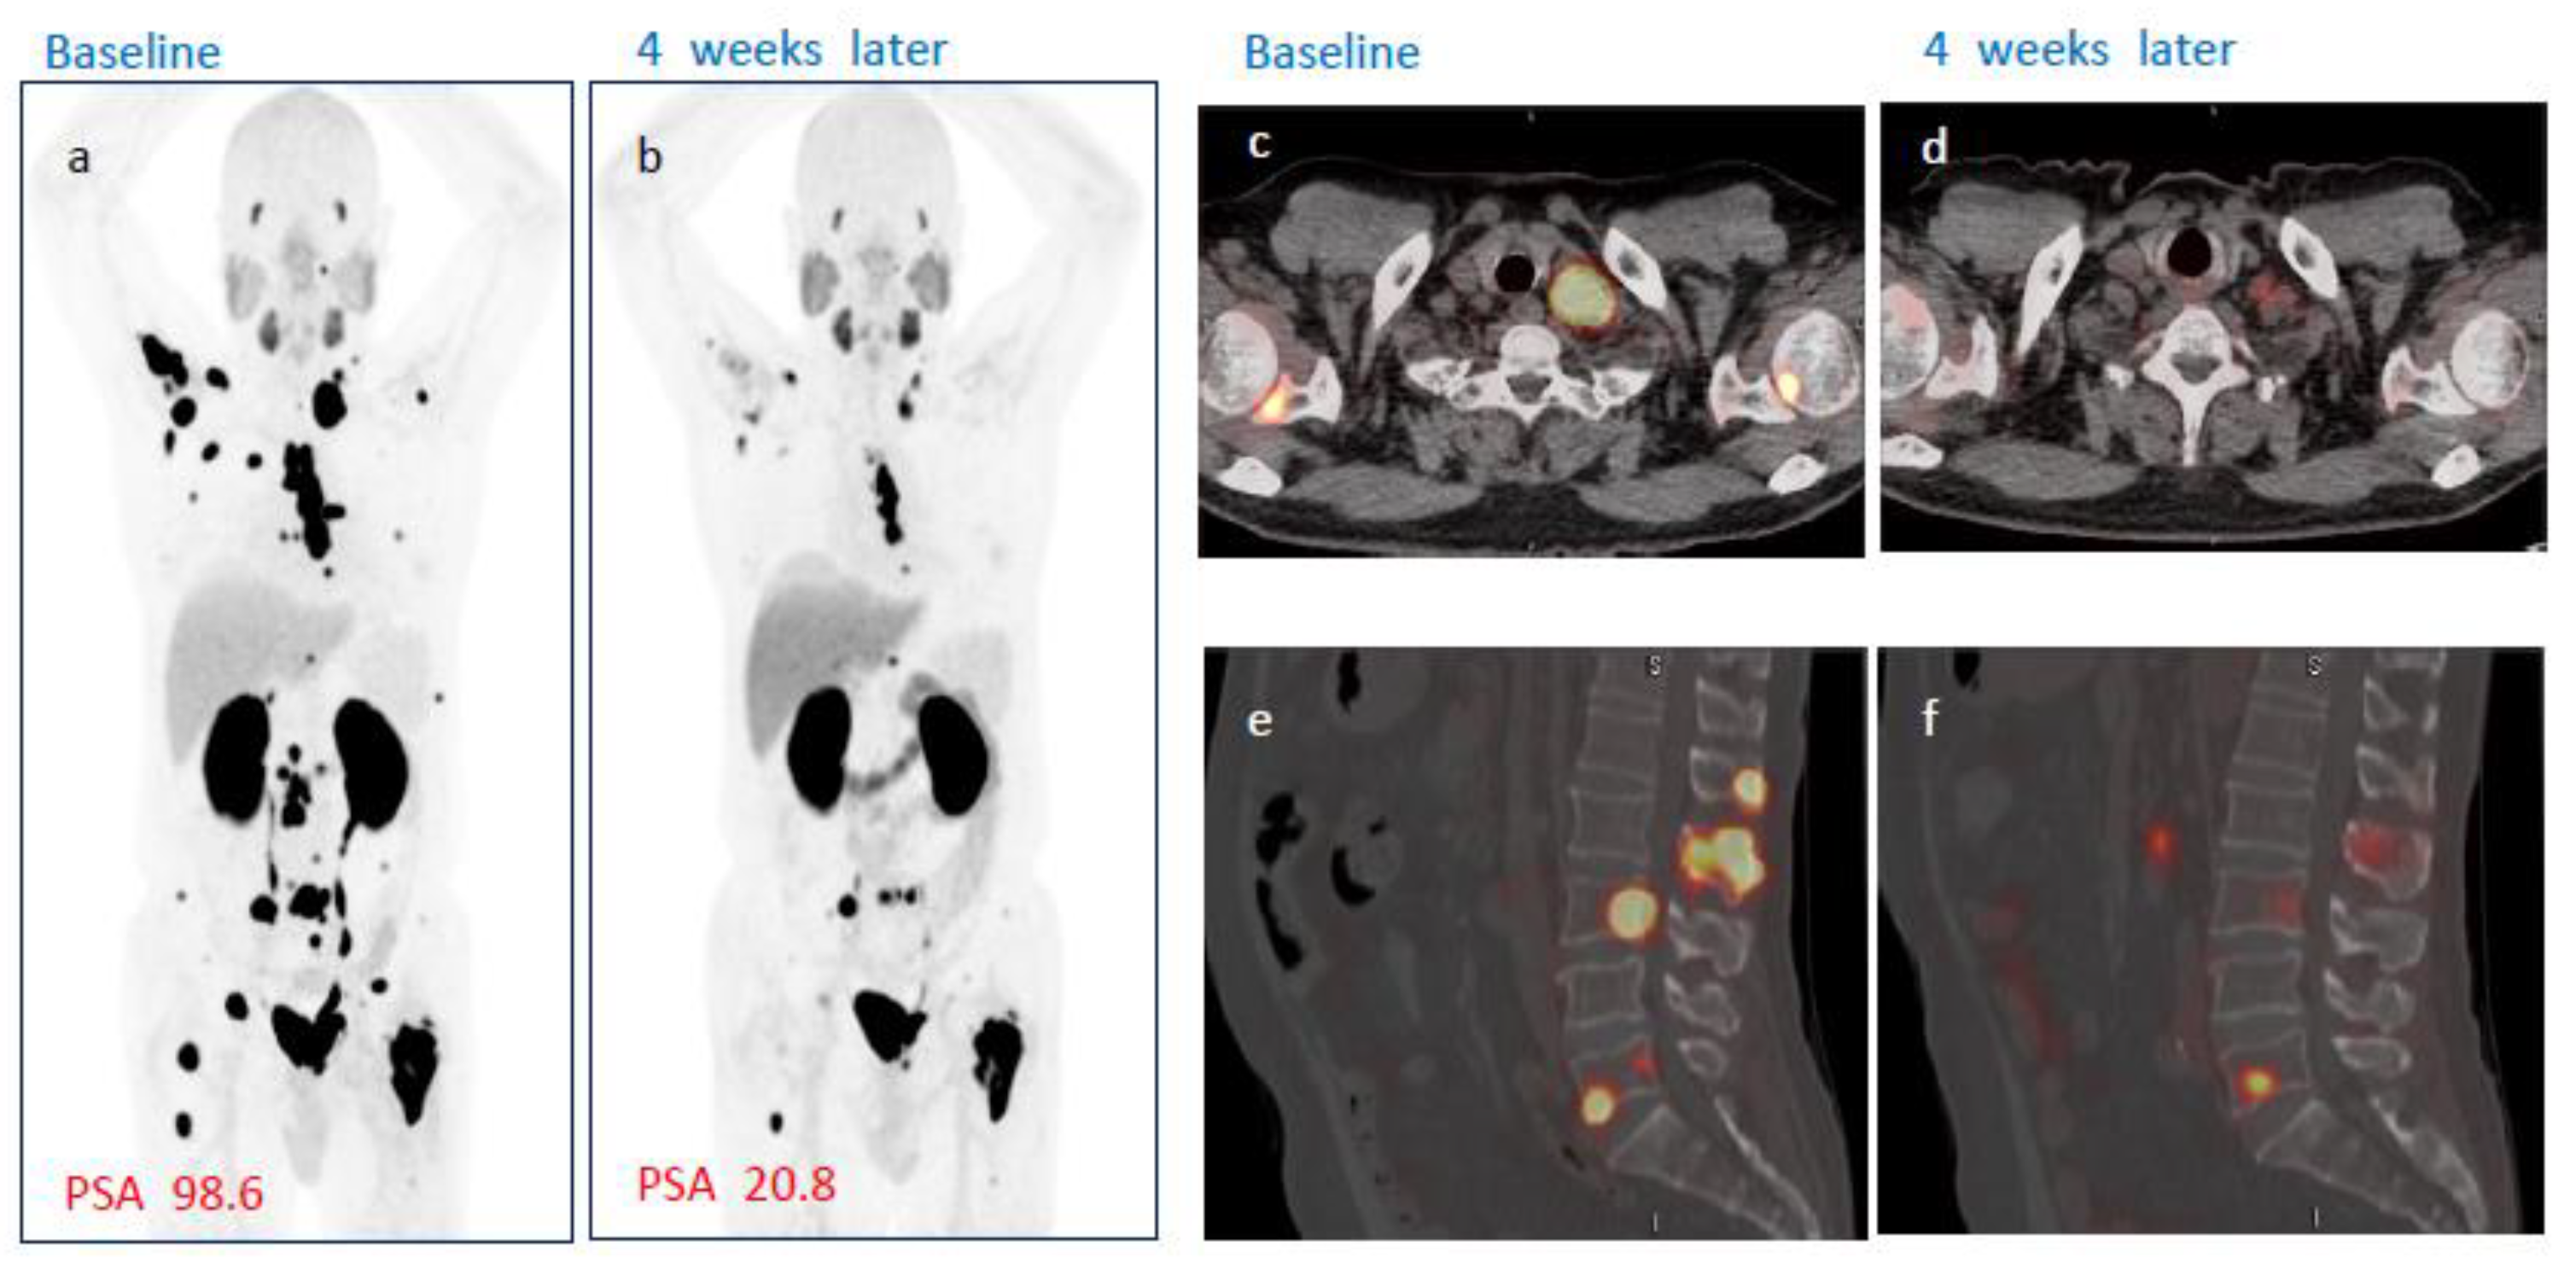

No patient demonstrated complete response on either week 4 or week 8 PSMA PET/CT after single administration of [177Lu]Ludotadipep. However, on week 8 PSMA PET/CT, 14 (56%) subjects had partial response and 10 subjects (40%) had stable disease (SD). One subject demonstrated progression on imaging. The overall objective response rate (ORR) was 40% at week 4 and 56% at week 8. The overall disease control rate (DCR) was 92% at week 4 and 96% at week 8 according to PSMA PET/CT findings. A case of a subject who received 3.7 GBq of [177Lu]Ludotadipep is shown in Figure 3, and another case of a subject who received 4.6 GBq is shown in Figure 4.

Figure 4.

A case of a subject showing response to [177Lu]Ludotadipep. (a,c,e) Baseline [18F]Florastamin PSMA PET/CT MIP, fused axial and sagittal images. (b,d,e) PSMA PET/CT images four weeks after administration of [177Lu]Ludotadipeps (a,b) MIP images show decreased tumor burden in the bone lesions and lymph nodes. (c,d) Axial fused PSMA PET/CT images show marked regression of left supraclavicular lymph node and bone metastases. (e,f) Sagittal PSMA PET/CT images show decreased uptake in the spine lesions.